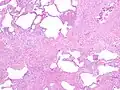

Histology

The histologic hallmarks of UIP, as seen in lung tissue under a microscope by a pathologist, are interstitial fibrosis in a "patchwork pattern", honeycomb change and fibroblast foci (see images below).[6] [7]

- Appearance of honeycomb change in a surgical lung biopsy at low magnification. The dilated spaces seen here are filled with mucin. Hematoxylin-eosin stain, low magnification.